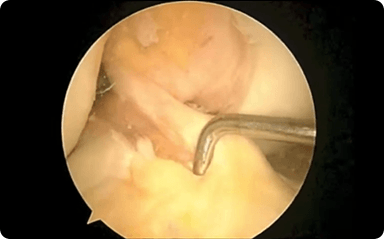

Robotic-assisted knee replacement surgery is an alternative to the conventional knee replacement procedure. It is performed using robotic-arm technology that allows your surgeon to precisely perform the surgery through a smaller incision as compared to traditional surgery. Dr. Liddell performs both total knee and partial knee replacement in a minimally invasive manner with precision under robotic assistance.

Dr. Travis R. Liddell is a board-certified orthopedic surgeon with more than 20 years of experience performing complex orthopedic procedures and helping patients restore mobility, strength, and quality of life. Over the course of his career, he has performed thousands of joint replacement and arthroscopic procedures, including more than 1,000 advanced robotic-assisted knee replacements.